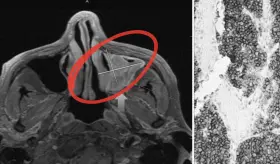

Las prótesis antiguas de metal con metal pueden liberar partículas mic...